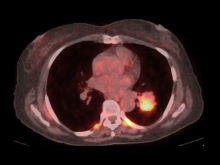

The video-assisted thoracoscopic surgery (VATS) approach used to perform lobectomy is widely accepted as a superior alternative to open thoracotomy. This is due to the following benefits: less postoperative pain, lower surgical morbidity, fewer complications, shorter hospital stays, and lower costs (6, 7). Video-assisted thoracoscopic pneumonectomy was first described by Walker in 1994 (8). After that, few reports of thoracoscopic pneumonectomy were published because the VATS approach is associated with technical difficulties (9–11). The purpose of this video is to show the authors’ experience performing a left pneumonectomy using the biportal VATS approach.